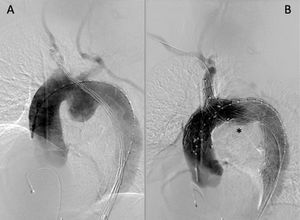

Los tamaños de prótesis implantadas se reflejan en la tabla 2. En la figura 2 se observan secuencias de la angiografía de control antes y después de la exclusión del aneurisma del segundo paciente.

Se realiza angiografía de control para comprobar la correcta aposición de los injertos, la exclusión de la patología y la permeabilidad de los TSA, fluoroscopia para retirada de material endovascular.